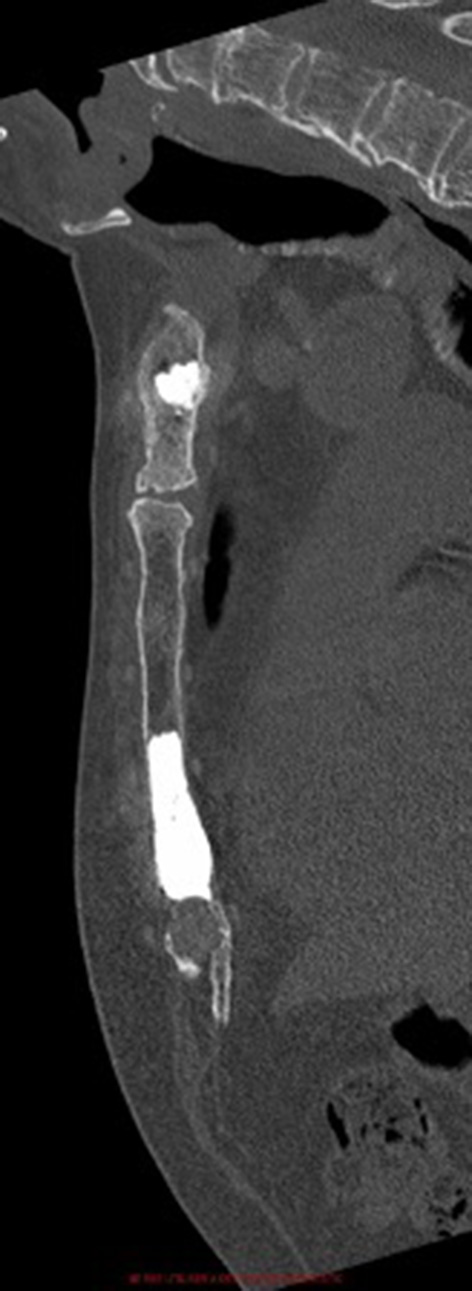

Figure 4

Post-operative sagittal computed-tomography image of patient 1.

Cementoplasty Procedures

The procedure time was 27 ± 12 minutes. The radiation exposure was 0.13 ± 0.04 mGy. During the procedure, 3 ± 3 mL of cement were injected. Figures 1–4 depict example of pre- and postinterventional CT findings.